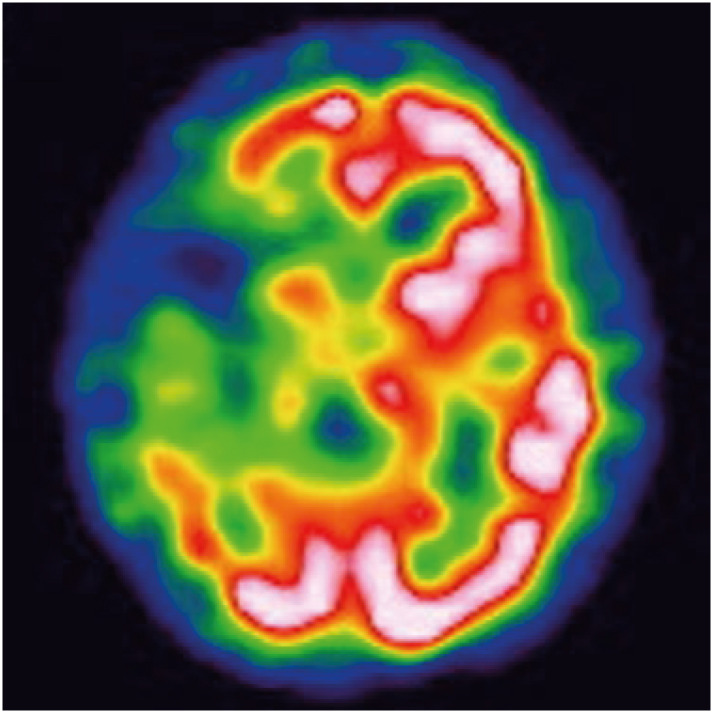

Crossed aphasia (CA) is a type of aphasia caused by cerebral hemispheric lesions on the same side of the dominant hand. The prevalence of CA is extremely rare. To the best of our knowledge, this is the first case report in Korea to conduct 6 years of long-term speech therapy in a case of a patient with CA. The patient was a 57-year-old right-handed man with aphasia caused by extensive acute infarction in the right middle cerebral artery territory. He presented with global aphasia, right-left disorientation, and agraphia. Language function recovered in the first 6 months and then plateaued.